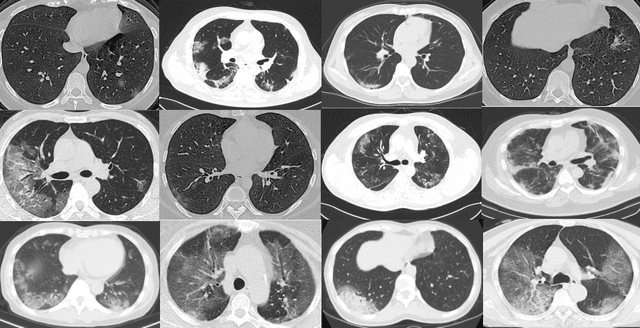

CT scans are promising in providing accurate, fast, and cheap screening and testing of COVID-19. In this paper, we build a publicly available COVID-CT dataset, containing 275 CT scans that are positive for COVID-19, to foster the research and development of deep learning methods which predict whether a person is affected with COVID-19 by analyzing his/her CTs. We train a deep convolutional neural network on this dataset and achieve an F1 of 0.85 which is a promising performance but yet to be further improved. The data and code are available at https://github.com/UCSD-AI4H/COVID-CT